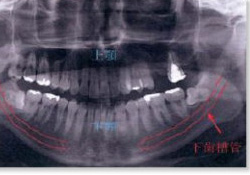

下顎の骨の中には、下歯槽管というトンネルがあり、下顎の後ろの方から下唇の斜め下ぐらいまで続いています。この中には神経と血管が走行しており、この神経(下歯槽神経といいます)は、骨の中のトンネルを出た後、下唇周囲まで枝を伸ばし、主に歯の感覚や、下唇とその周囲の感覚を担当しています。抜歯の際に問題になるのは、智歯の根の先と下歯槽管の位置関係です。根の先がトンネル内に突出していた場合、抜歯によりトンネル内に穴があき、神経血管の損傷の原因になります。血管損傷時には、強い出血により抜歯を中止する事もあり得ます。

下歯槽管(赤線)は、下顎の後ろの方から下唇の斜め下ぐらいまで走行する。

智歯の根の先は下歯槽管から離れており、抜歯による血管神経損傷の可能性は低い